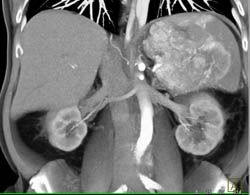

Islet Cell Tumor With Liver Metastases